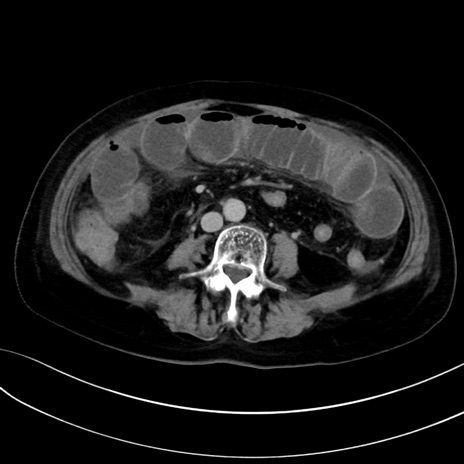

症例13 CT(横断像)1日半後